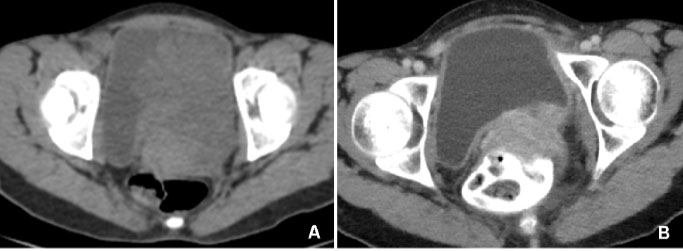

A 28-year-old female presented with massive hematuria with clots. She was seen at the major testing centers and was given massive blood transfusions. Hemoglobin dropped to 4–3.5 g/dL within days of transfusion. She was on treatment for endometriosis and primary infertility. She underwent laparoscopic bilateral oophorectomy and prolonged medical management with danazol, while hematuria continued and became worse. As she presented to us, a papillary lesion was seen projecting through the urethra. Cystoscopic evaluation showed a mass in the supratrigonal area and base. Ultrasound abdomen (USG) and magnetic resonance imaging (MRI) scan showed lesions involving the urinary bladder, uterus and pelvis (Figure 1). Contrast-enhanced computed tomography (CECT) abdomen showed involvement of both ureters in the lower one third, producing massive hydroureteronephrosis (HUN) (Figure 2). However, her creatinine remained stable, and percutaneous nephrostomy (PCN) was deferred. As the exsanguinating hematuria continued despite all therapeutic measures, we noticed a previous report in which a similar case was managed [1] and opted to follow the steps described there, in consultation with the radiation oncology team. With their support, we gave radiotherapy (RT) to the pelvis, as endometrial tissue is very highly radiosensitive. A radiation dose of 20 Gy in 10 fractions with 15 MV photons was delivered to the target. It was delivered as 200 cGy per fraction and 5 fractions a week, in 4 fields (AP, PA, left lateral, and right lateral), and the dose was prescribed to 100% isodense line, treating using 3D CRT technique (Figure 3). The targeted volume for RT was uterine myoma and normal endometrium, along with the lesion infiltrating into the bladder. The response of cessation of bleeding was swift. The HUN also resolved in two weeks. This occurred in the year 2017. The patient was monitored for three years, and now she is completely asymptomatic, except for irregular menstrual periods. The CT scan taken recently showed a normal bladder and upper tracts, and the pelvic endometriosis had disappeared completely (Figure 4).

Figure 2: Endometrial tissue infiltrating the ureter and causing obstruction, resulting in HUN.